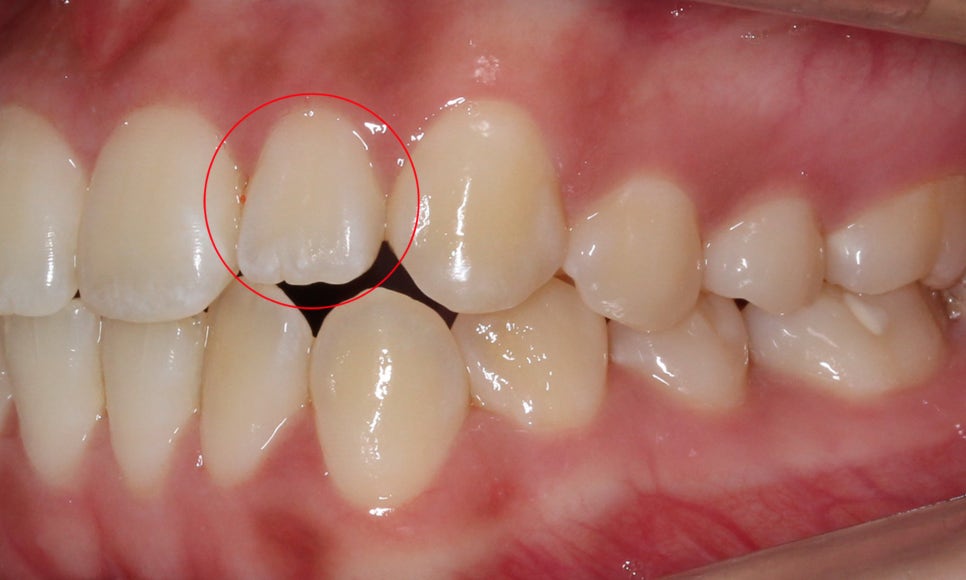

반대쪽 측절치 역시

길이가 짧아서 치아 끝이

거의 마모되지 않은 모습입니다~

윗니의 안쪽 면을 보면

작은 앞니(측절치)의 크기가

주변 치아보다 확실히 작은 모습인데요,

아랫니를 보시면

왜소치가 아님에도 치아 끝이

톱니처럼 울퉁불퉁한 것을 확인할 수 있습니다!

이렇게 왜소치가 원인이 아닌 경우

부정교합으로 인해 치아 끝이 맞물리지 않아

마멜론이 남아있을 수 있을 수 있습니다.